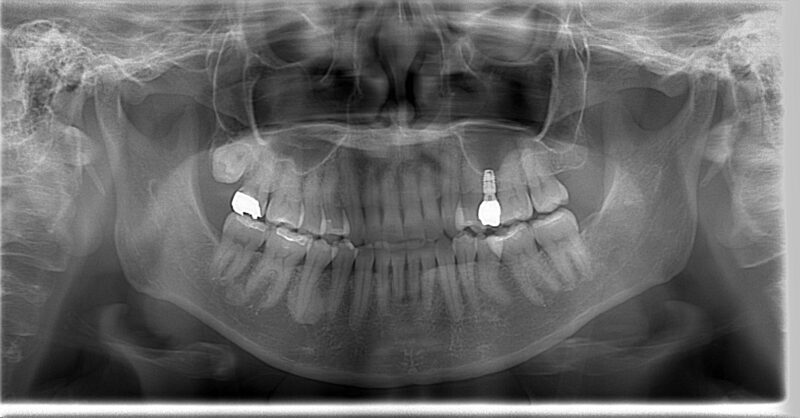

そして、すべての治療が完了してから6年が経過した現在のレントゲン写真がこちらです。

術前の写真と見比べてみてください。左上にインプラントが入り、しっかりと安定しているのがお分かりいただけると思います。銀歯も白い歯に変わり、見た目も自然で美しくなりました。

短いながらも、インプラントが周りの骨としっかりと結合し、安定した土台となっている様子が確認できます。これにより、Aさんは左右の奥歯で均等に、力強く噛むことができるようになりました。

そして何よりも嬉しい変化は、Aさんを長年苦しめていた耳鳴りと頭痛が、すっかり解消されたことでした。「あれだけ悩んでいたのが嘘のようです。もっと早く相談すればよかった」と、晴れやかな笑顔で話してくださった時の表情は、今でも忘れられません。